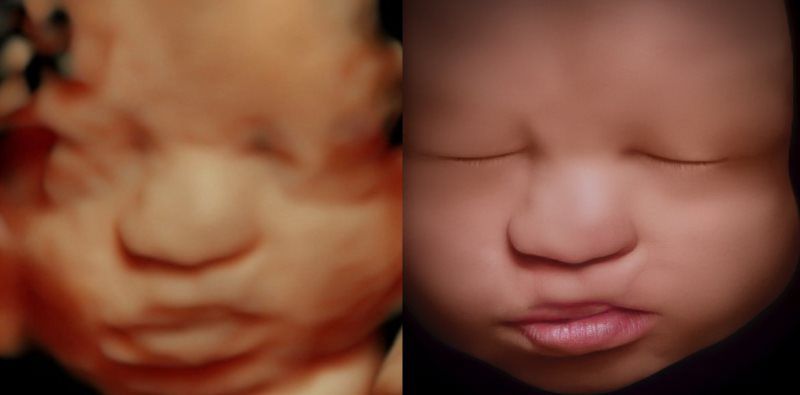

A Little Insight is proud to announce that we now offer 8K technology. This is the most realistic & amazing view of your unborn baby.

A Little Insight is an elective ultrasound center dedicated to providing a private experience that focuses on you and your baby, and we believe that every parent deserves to maximize their prenatal experience. Our 3D/4D & 5D ultrasounds provide an opportunity for you to see your baby not only in still image but in real-time motion. Why wait until your baby is born to celebrate his/her life?

A Little Insight 3D/4D/5D Ultrasound is unique because we truly offer the finest 3D/4D & 5D prenatal experience available. We combine cutting-edge technology with a family theater environment to bring you incredible images of your unborn baby in the womb. Best of all, we offer an unparalleled bonding experience that you and your family can cherish for a lifetime!